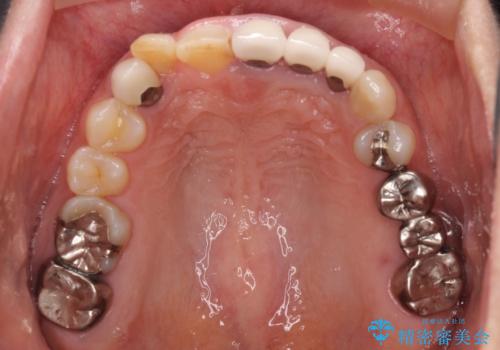

- 右下の奥歯が痛く、全体的に咬み合わせがおかしい気がするとのことで来院された患者様です。

診察したところ、上顎前歯に過剰歯があることで上顎歯列が大きくなり、上下の歯が奥歯の一部でしか咬み合っていない状態でした。

そのため右下の奥歯に強い負担が生じていて、むし歯が大きかったこともあり、抜歯が必要な状態でした。

咬み合わせ改善のため、前歯の過剰歯を抜去し、ワイヤー矯正にて歯列と咬み合わせることとしました。

左上の奥歯のブリッジや前歯のセラミッククラウンはいったん除去し、矯正治療後に補綴治療を行うこととしました。